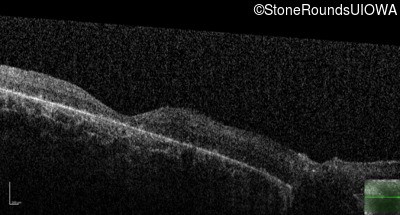

Optical Coherence Tomography - Right - Hand Motion

Exemplar / OCT Stack